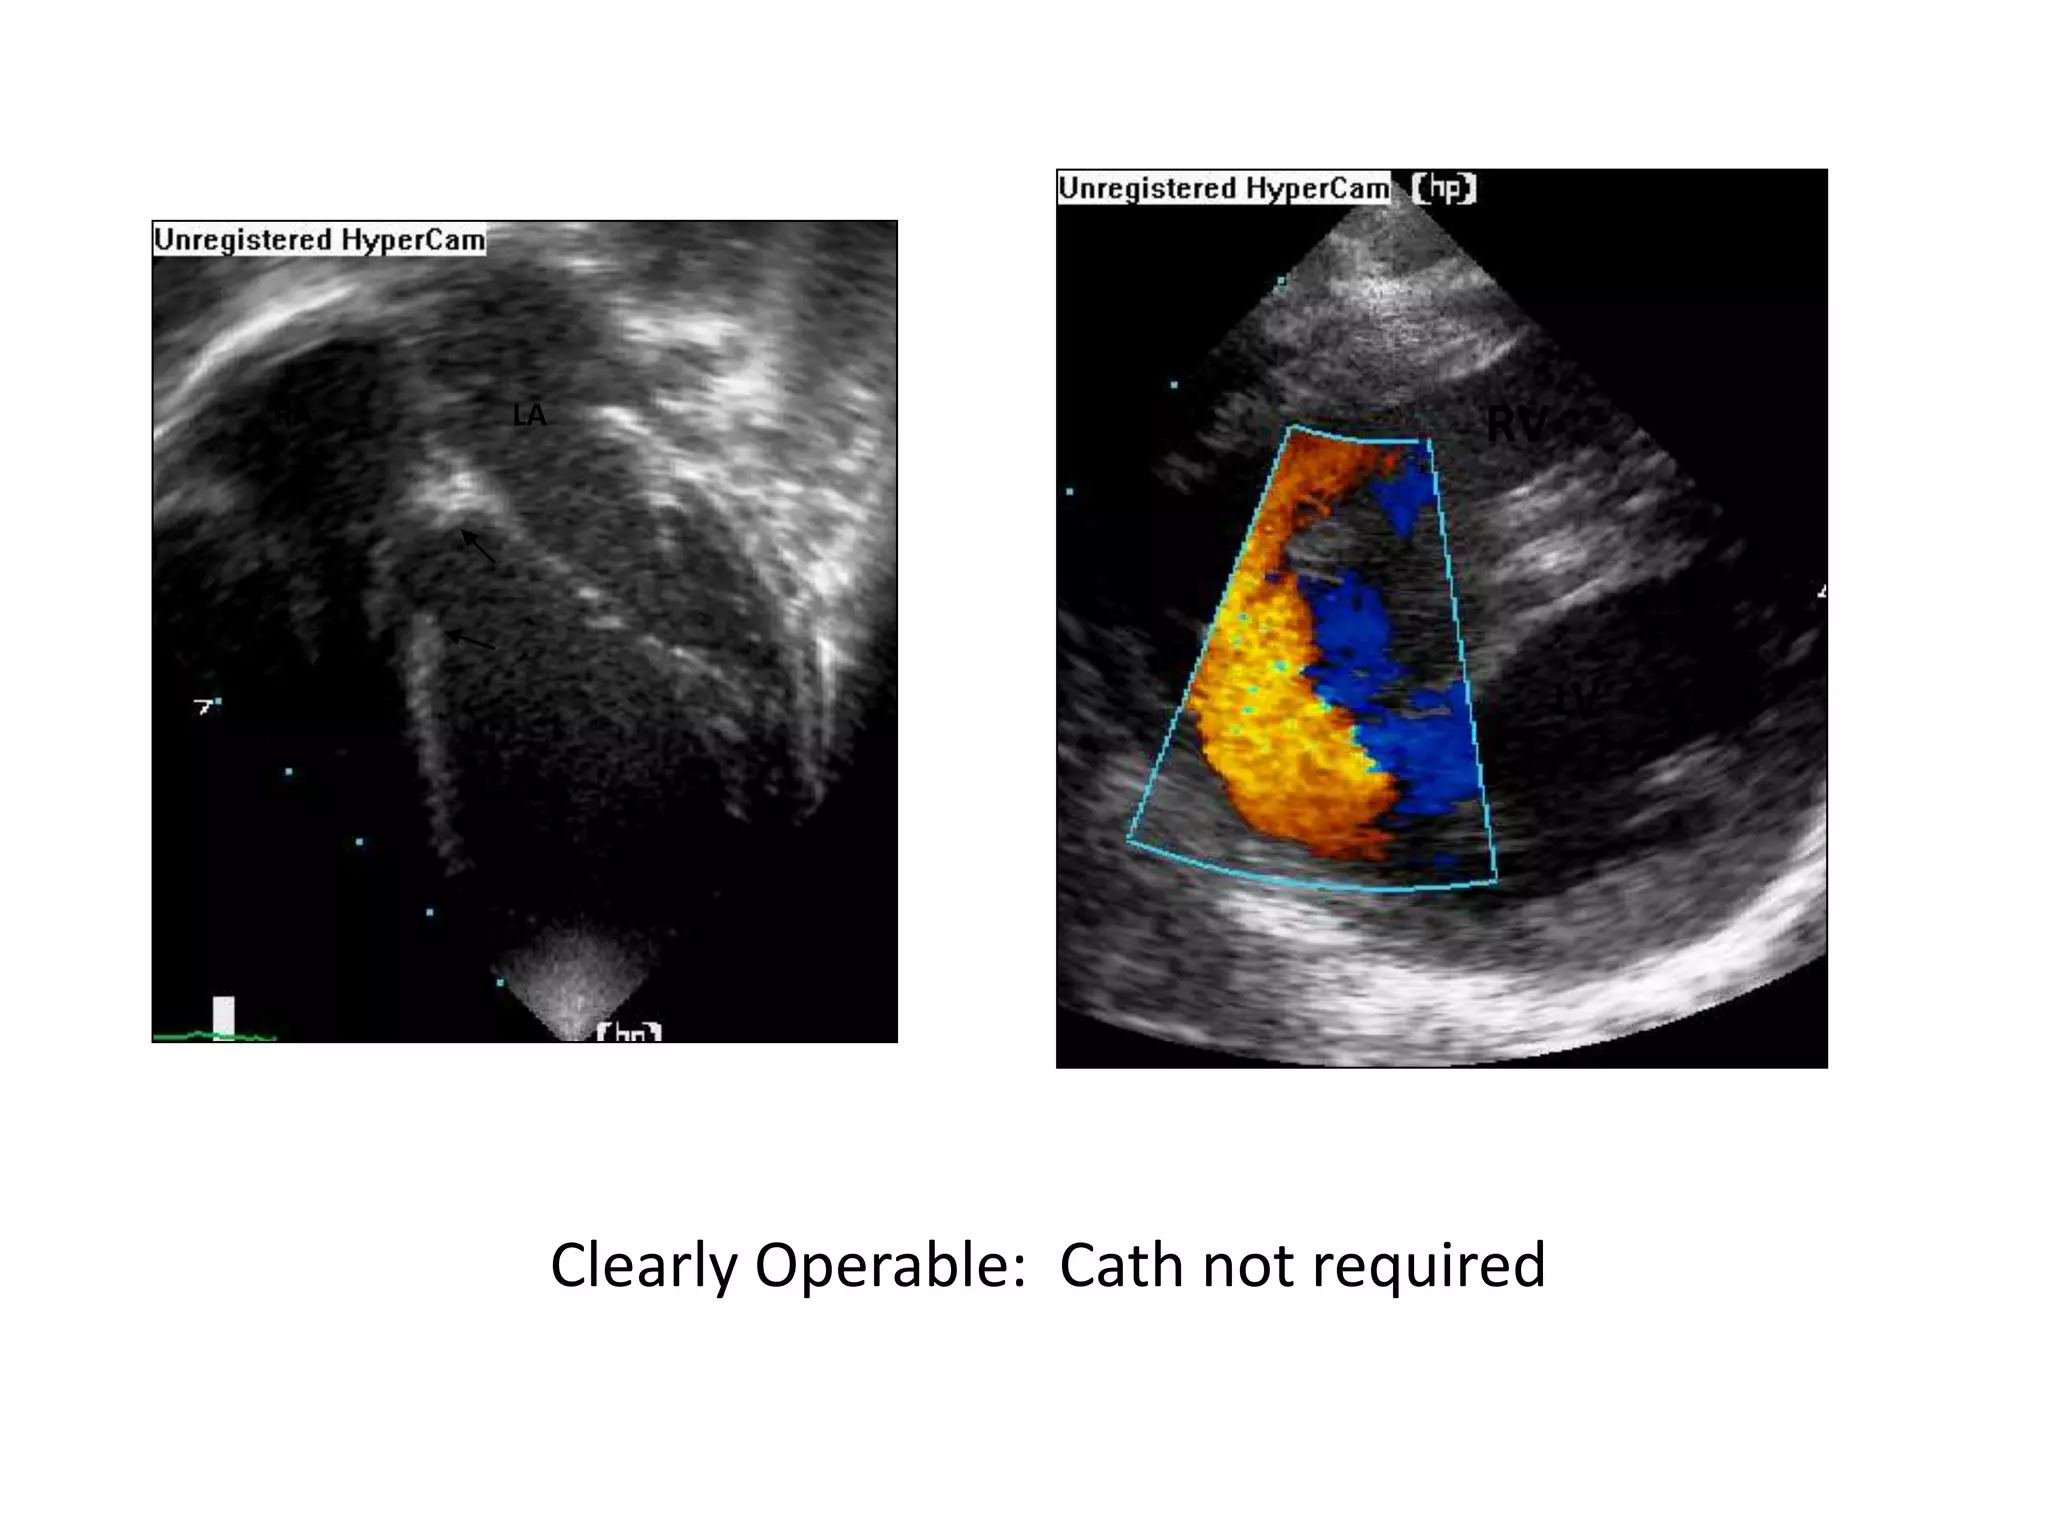

LV

RVLA

RA

RV

Clearly Operable: Cath not required

CLINICAL ASSESSMENT • Serialassessment by multiple experienced clinicians improves the reliability of clinical examination as a tool in determining operability • The presence of ‘clinical cyanosis’ or saturations <90% is a strong predictor of inoperability whereas the clear detection of a MDM on serial assessment strongly favours operability.